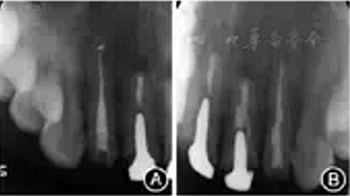

圖6 患者顯微根尖手術(shù)再治療過程 A:齦緣下方扇形水平切口,翻開組織瓣;B:根尖切除后;C:使用三氧化礦物凝聚體根尖倒充填后檢查;D:手術(shù)切口縫合術(shù)后根尖X線片顯示根充糊劑少量超填,根充恰填,倒充填根尖3 mm致密,與樁核末端之間尚有部分空隙(圖7)。

圖7 患者再治療完成后即刻根尖X線片 A:糊劑少量超填,根尖3 mm倒充填致密;B:恰填,根尖3 mm倒充填致密。